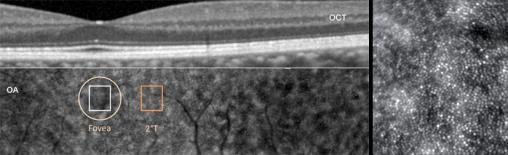

Image en optique adaptative (OA) passant par le centre de la macula et correspondant à la coupe en tomographie en cohérence optique (OCT).À droite, l’agrandissement d’une zone située à 2° en temporal du centre de la fovéa montre la mosaïque normale des photorécepteurs (précisionde 2 μm). Clichés dus à l’obligeance du Pr Michel Paques.